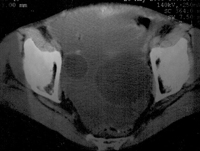

Cáncer de ovario (ecografía)

Cáncer de ovario (resonancia magnética nuclear)The incidence of uterine neck cancer remains constant at all ages in women, whereas ovarian cancer and endometrial cancer increase considerably during the perimenopausal years, and are by far the most frequent after the age of 50.

At present, mortality rates due to ovarian cancer clearly exceed combined mortality due to cancer of the uterine neck and endometrial cancer.